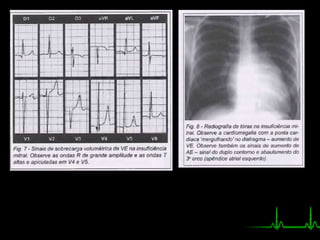

• Eletrocardiograma:

• Radiografia: